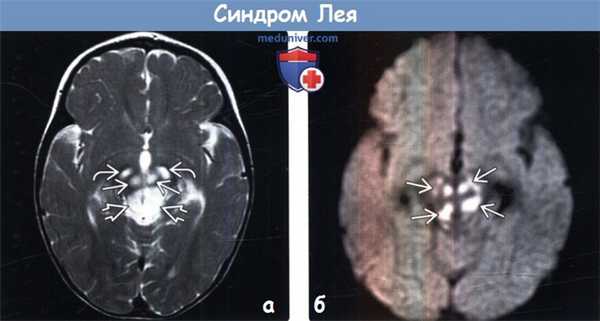

(а) МРТ, Т2-ВИ, аксиальный срез: отмечается повышение интенсивности сигнала от ножек мозга, красных ядер и покрышки среднего мозга (включая периакведуктальное серое вещество). Эти структуры являются частой локализацией поражения ствола мозга при синдроме Лея.

(б) МРТ, ДВИ, аксиальный срез: определяется ограничение диффузии (гиперинтенсивные участки) в пораженных участках среднего мозга. Ограничение диффузии указывает на острую стадию поражения, в то время как повышение диффузии больше указывает на хроническую стадию поражения.